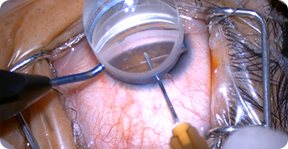

本专科秉承临床科学问题为中心,重视临床和基础研究的转化医学研究,着力提高青光眼诊疗水平。注重科普宣教,成立青光眼俱乐部,定期开展科普讲座;成立24小时眼压监测病房,为青光眼患者提供专业规范、客观准确的眼压波动曲线,指导临床判断。本专科常规开展复合式小梁切除术,青光眼365足球盘口网站联合手术,Ahmed青光眼引流阀植入术,穿透性粘小管成型术,360度小梁切开术(GATT、MAT)等各类微创抗青光眼手术;开展YAG虹膜激光和532激光房角成型术治疗闭角型青光眼,选择性激光小梁成形术(SLT)激光治疗开角型青光眼;在恶性青光眼的治疗以及超声睫状体成形术(UCP)治疗难治性青光眼方面具有丰富的临床经验。中西医结合治疗为青光眼所致的视神经萎缩提供了新的有效途径。

- 复合式小梁切除术

- 超声乳化365足球盘口网站吸除人工晶状体植入联合 小梁切除术(大青白 PEI+Trab)

- 超声乳化365足球盘口网站吸除人工晶状体植入联合房角分离 及房角切开术(小青白 PEI+GSL+GT)

- Ahmed青光眼引流阀植入术

- 穿透性粘小管成型术(PCP)

- 360度小梁切开术(GATT、MAT)